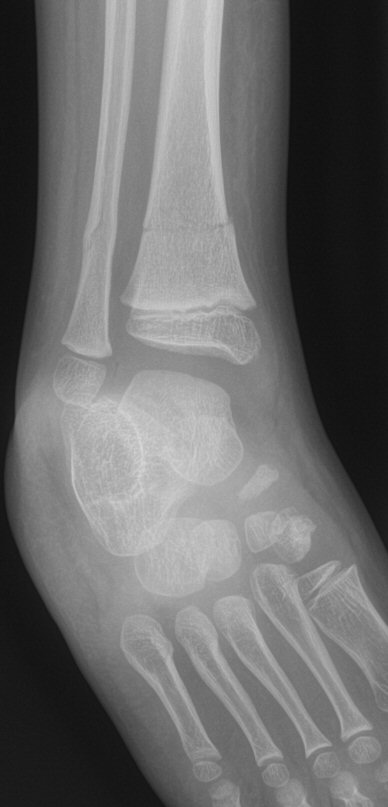

Distala tibiametafys- och fibuladiafysfrakturer. Behandlades icke-kirurgiskt.